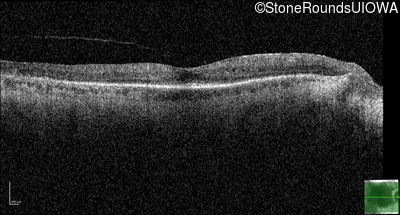

Optical Coherence Tomography - Right - 20/25 -1

Exemplar / OCT Stack